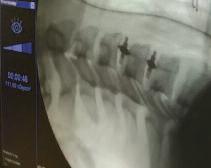

Σε αρκετούς ασθενείς ανιχνεύεται το

αντιγόνο HLA - B27 ,το οποίο υποβοηθεί την διάγνωση Μεγάλη βοήθεια στη διάγνωση προσφέρουν οι ακτινογραφίες κυρίως των ιερολαγονίων αρθρώσεων, των οποίων η προσβολή είναι παθογνωμονική της νόσου Συνήθως οι ιερολαγόνιες προσβάλλονται εξαρχής κάτι όμως που δεν φαίνεται πάντα στην απλή

ακτινογραφία και απαιτείται μαγνητική τομογραφία ιερολαγονίων αρθρώσεων Αυτή μπορεί να δείξει χαρακτηριστικές βλάβες της νόσου, όπως οστικό οίδημα, διαβρώσεις κ α

Με την πάροδο του χρόνου μπορεί να διαπιστωθούν ακτινολογικές αλλοιώσεις σε όλες τις μοίρες της σπονδυλικής

στήλης, όπως αγκύλωση των αρθρώσεων και δημιουργία συνδεσμοφύτων κάτι το οποίο μπορεί να οδηγήσει τελικά στην εικόνα «bamboo spine» Ευτυχώς σήμερα με την εφαρμογή των νεότερων θεραπειών και την πρωιμότερη διάγνωση της νόσου σπανίως συναντάμε αυτή την εικόνα στους νέους ασθενείς. Θεραπεία Μεγάλη σημασία έχει η έγκαιρη διάγνωση της Α Σ και η παραπομπή του ασθενούς σε ρευματολόγο, ώστε με την κατάλληλη θεραπεία να αποφευχθούν οι μόνιμες βλάβες που οδηγούν σε κύφωση, αγκυλώσεις αρθρώσεων κ.α. Είναι σημαντική, επίσης και η μη φαρμακευτική θεραπεία με ειδικές ασκήσεις που μπορούν μόνοι τους οι ασθενείς να κάνουν Επίσης, βοηθάει πολύ η κολύμβηση καθώς και η φυσικοθεραπεία